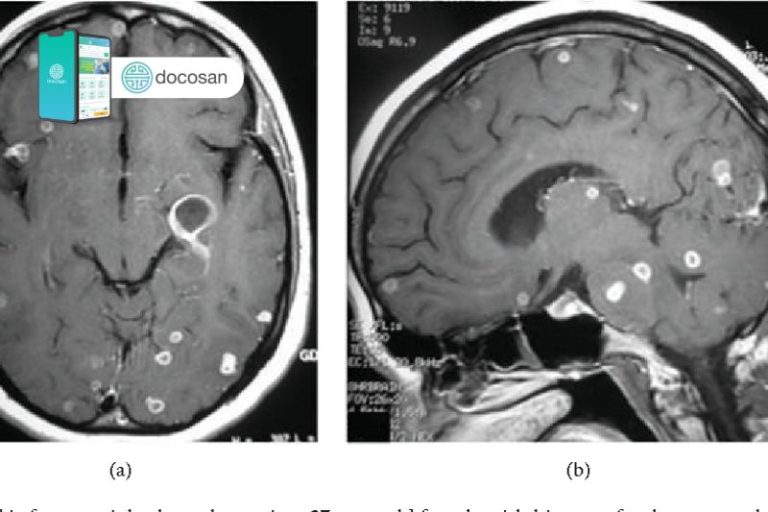

- X-quang phổi: trên phim x-qaung có thể thấy tổn thương sơ nhiễm thường nằm ở thùy dưới phổi phải. Đây là một nốt mờ tròn, không đồng đều bờ không rõ, đường kính từ 5 – 20mm.